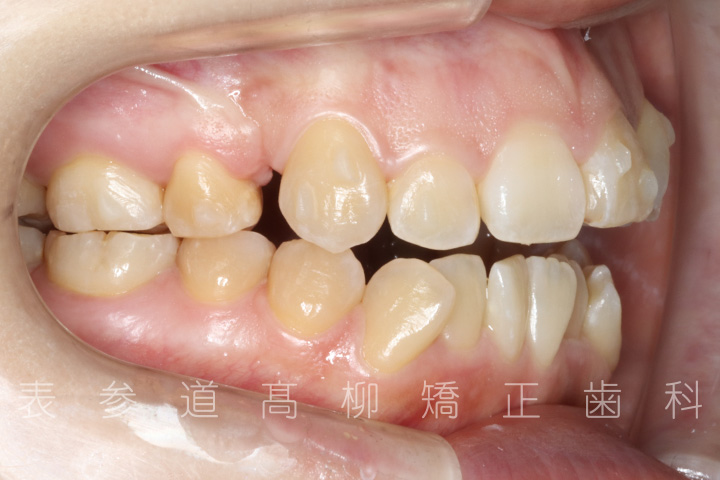

前歯のガタガタ感と開咬でお悩みの患者様の症例をご紹介いたします。

• 初診

・前歯部開咬

・上下前歯部叢生(凸凹歯並び)

・金属アレルギーのため、マウスピース型矯正装置を多く設定し、ワイヤーでの矯正治療期間を短縮

・上顎左右第一小臼歯、下顎左右第二小臼歯を抜歯の抜歯

・マウスピース型矯正装置と歯科矯正用アンカースクリュー(i-station)を併用し、上顎臼歯部を圧下

・歯科矯正用アンカースクリュー(i-station)を併用し、前歯部を後方へ移動する

・歯科矯正用アンカースクリューを併用し、口下顎大臼歯の近心移動(前方への移動)

・上下歯列の緊密な咬合関係の確立に顎間ゴムを併用(装着時間20時間以上/日)